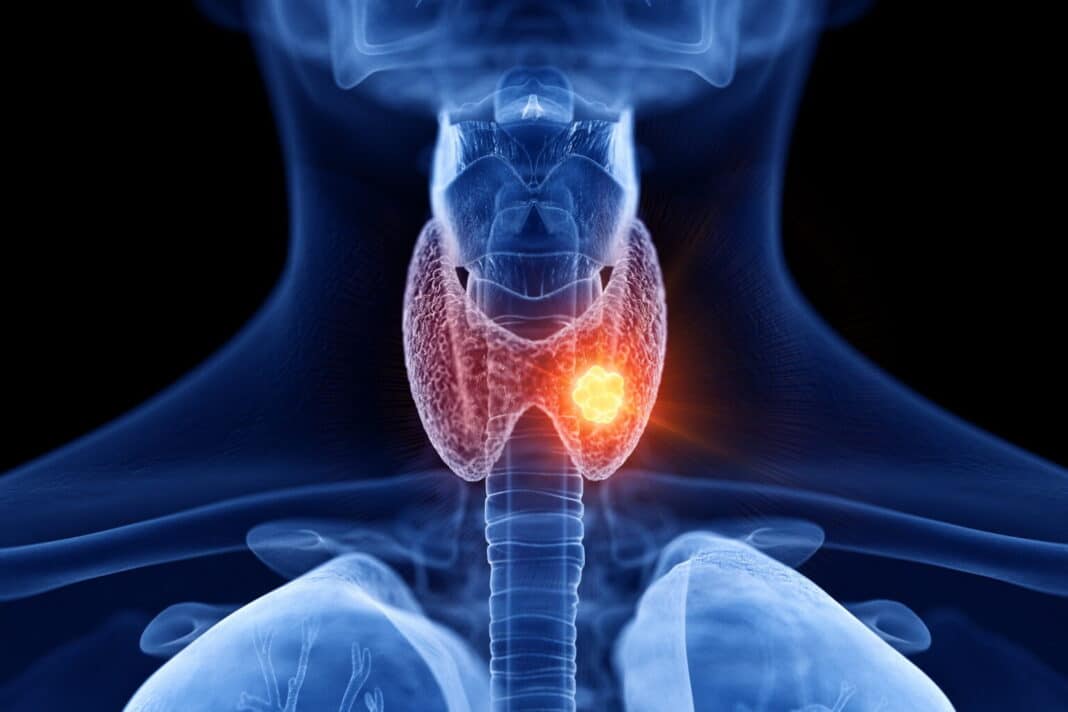

Ο καρκίνος του θυρεοειδούς είναι η πιο συχνή κακοήθεια των ενδοκρινών αδένων. Στοιχεία δείχνουν πως αυτή η μορφή του καρκίνου πλήττει τις γυναίκες τρεις φορές πιο συχνά απ’ ότι τους άνδρες. Μάλιστα, τα τελευταία χρόνια οι διαγνώσεις καρκίνου του θυρεοειδούς ολοένα και αυξάνονται σε όλον τον κόσμο. Τόσο σε ενήλικες και παιδιά. Η αύξηση της επίπτωσης της συγκεκριμένης κακοήθειας έχει διαπιστωθεί ότι είναι μεταξύ των υψηλότερων από κάθε άλλη μορφή καρκίνου σε χώρες και των 5 ηπείρων.